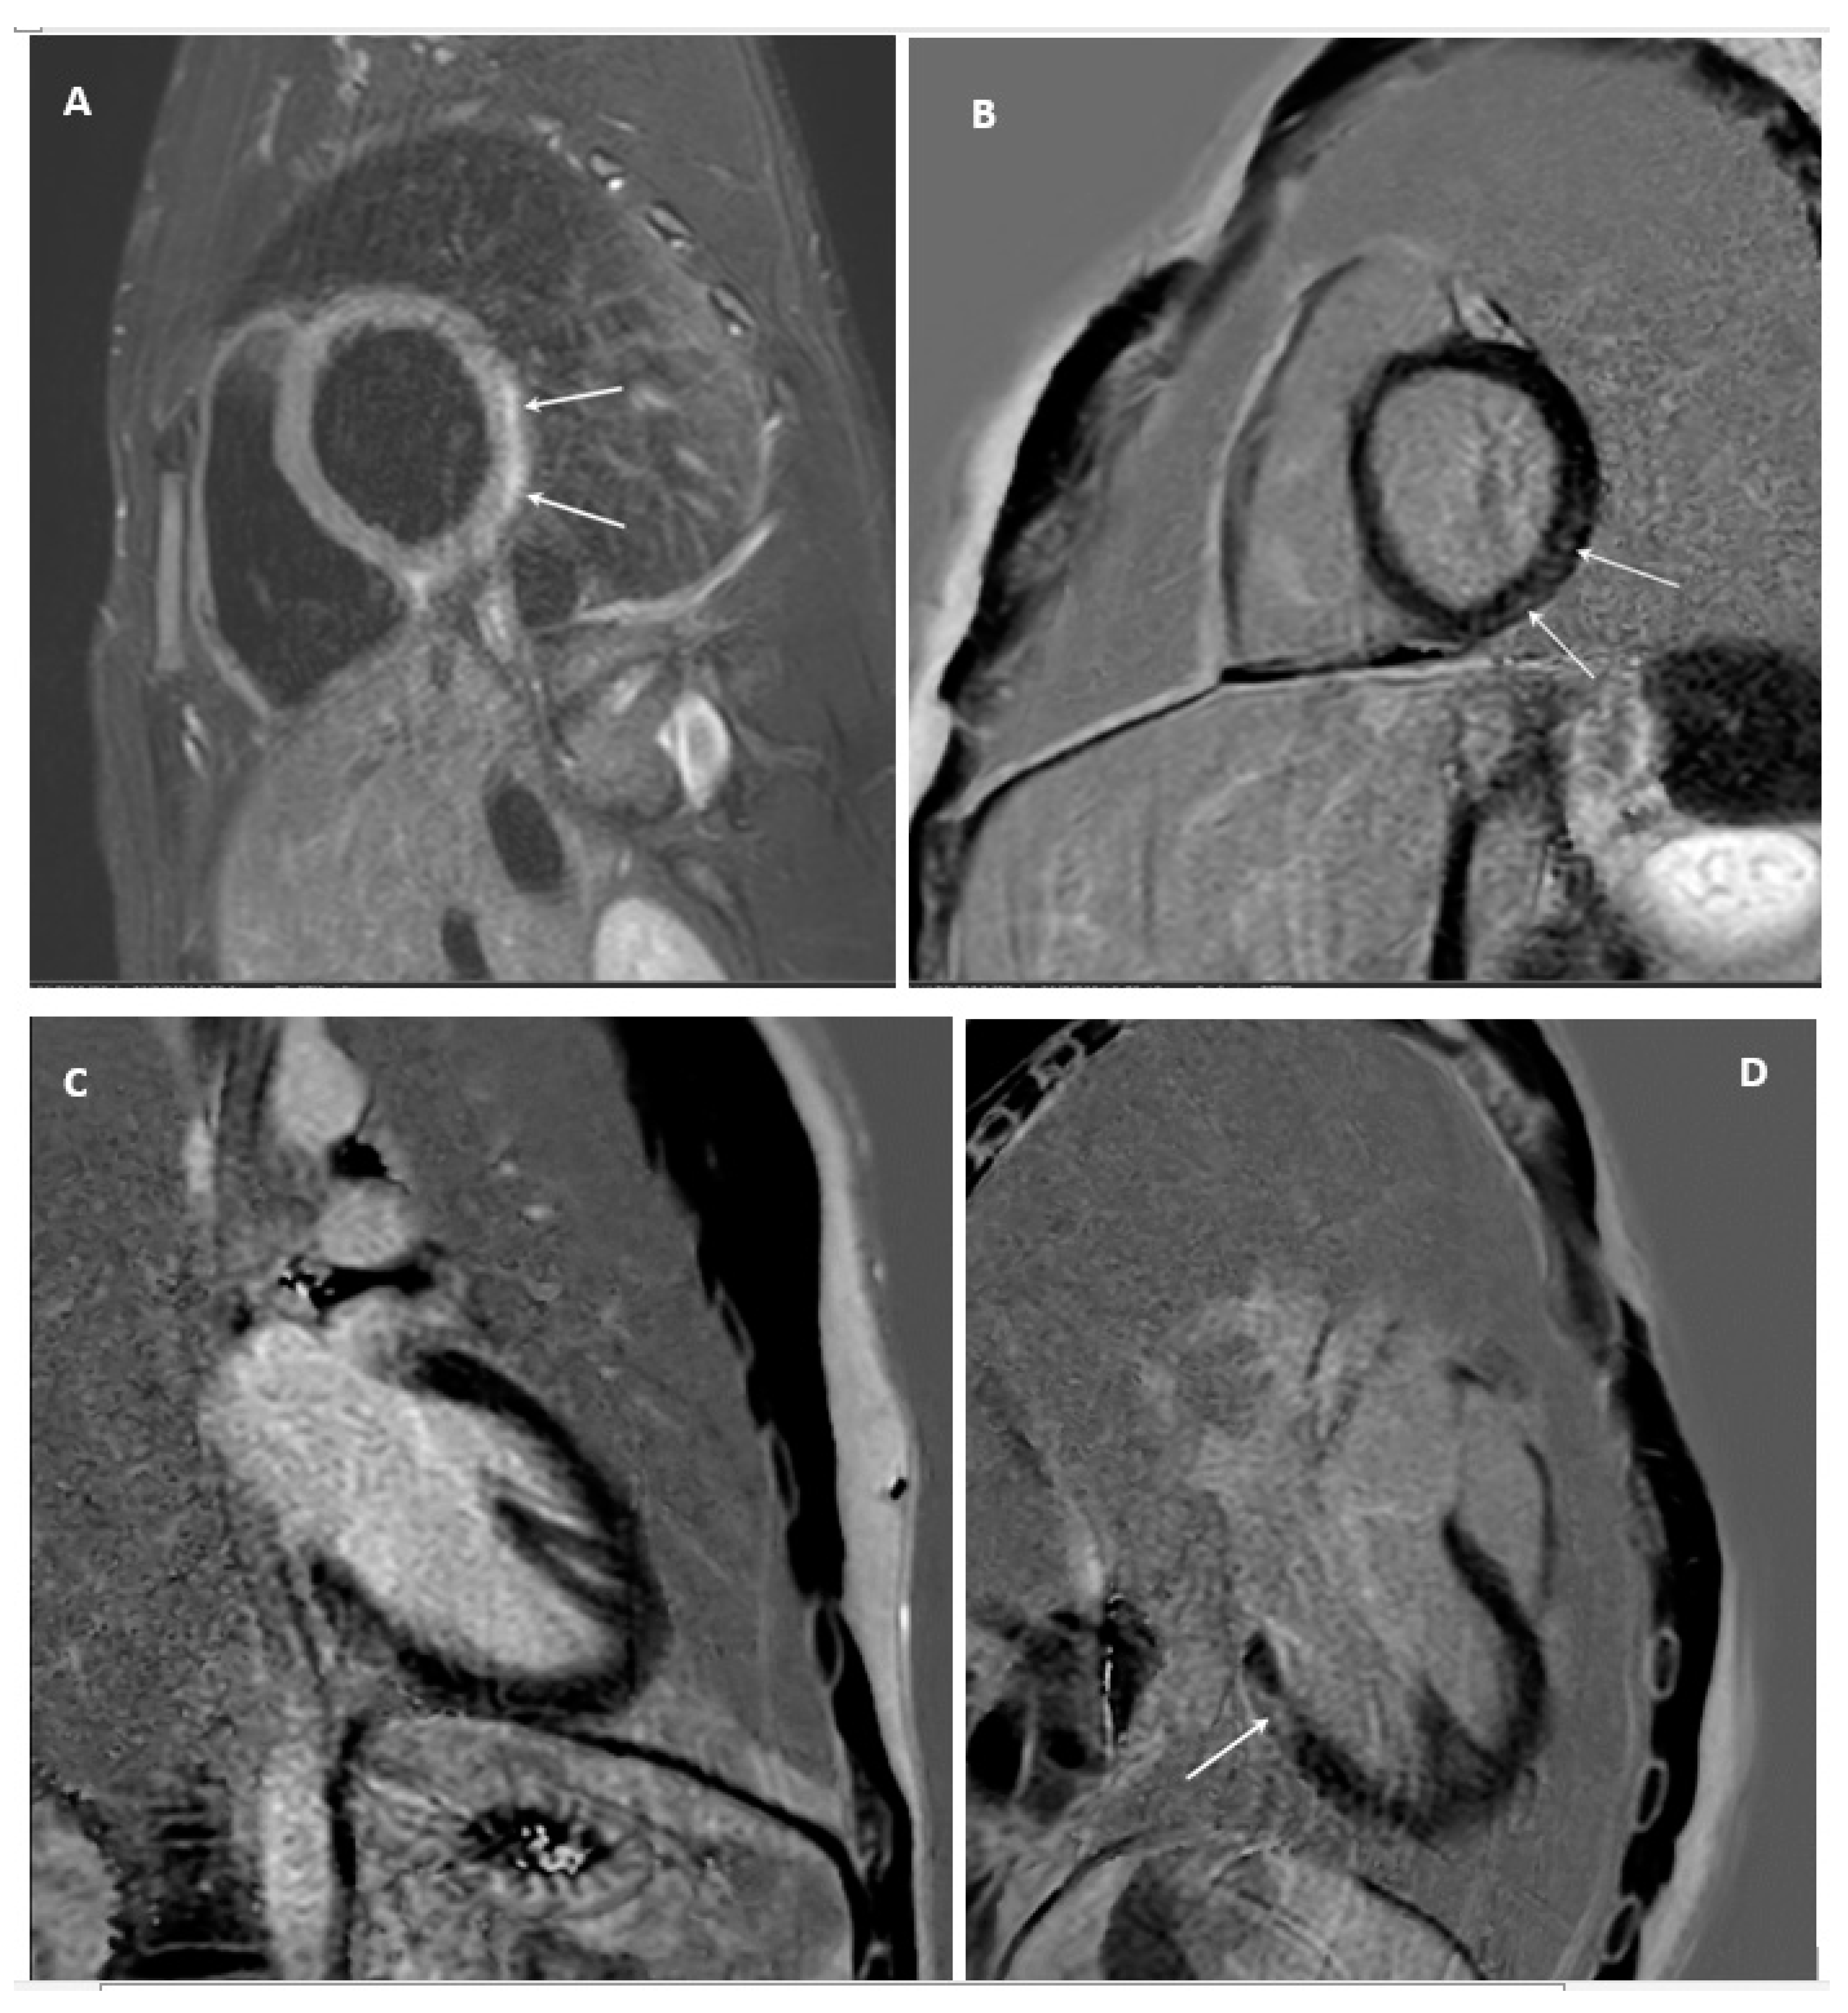

2. Case Report